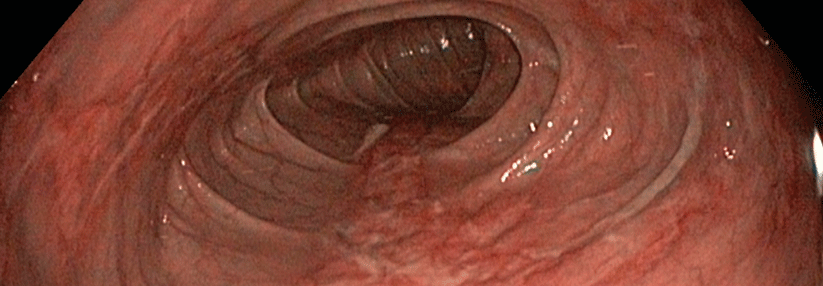

Typische Anzeichen sind Bauchschmerzen, Durchfall oder Verstopfung nach einer Mahlzeit. Typische Anzeichen sind Bauchschmerzen, Durchfall oder Verstopfung nach einer Mahlzeit. © iStock/krisanapong detraphiphat